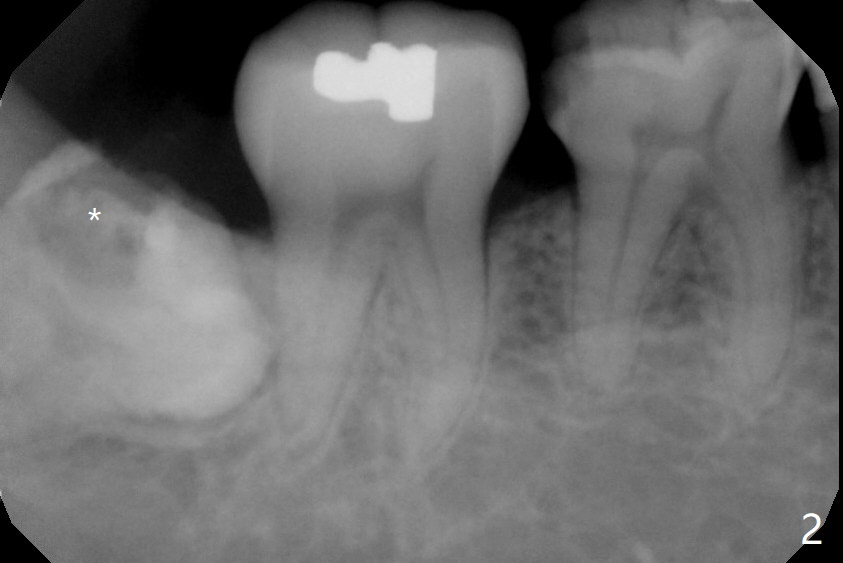

A 51-year-old woman presents to clinic because of infection in the lower right third molar (Fig.1). Although the tooth seems to be fully bony impaction, there is a sinus track with light purulent discharge after oral Amoxicillin for 5 days. In fact there is subgingival caries (Fig.2 *). The accessory incision is made mesiobuccal of #31 due to horizontal impaction. In fact the tooth is buccal and slightly mesial to #31. The impacted tooth requires several sections to be removed. Osteogen Plug is placed because of the thin bone between #31 and 32 (Fig.3 O).